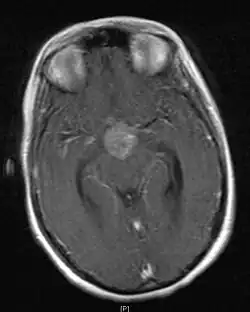

• Mainly located in midline structures, suprasellar region or pineal gland, also basal ganglia and hypothalamus

• Natural spread believed to be along subependymal lining of 3rd and 4th ventricles, leading to intraventricular relapse before spinal dissemination

Location